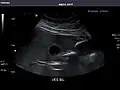

Kidneys: Right and left kidneys measure 11.5 cm and 12 cm in length respectively. No hydronephrosis. Small left lower pole kidney cyst.

Left kidney -